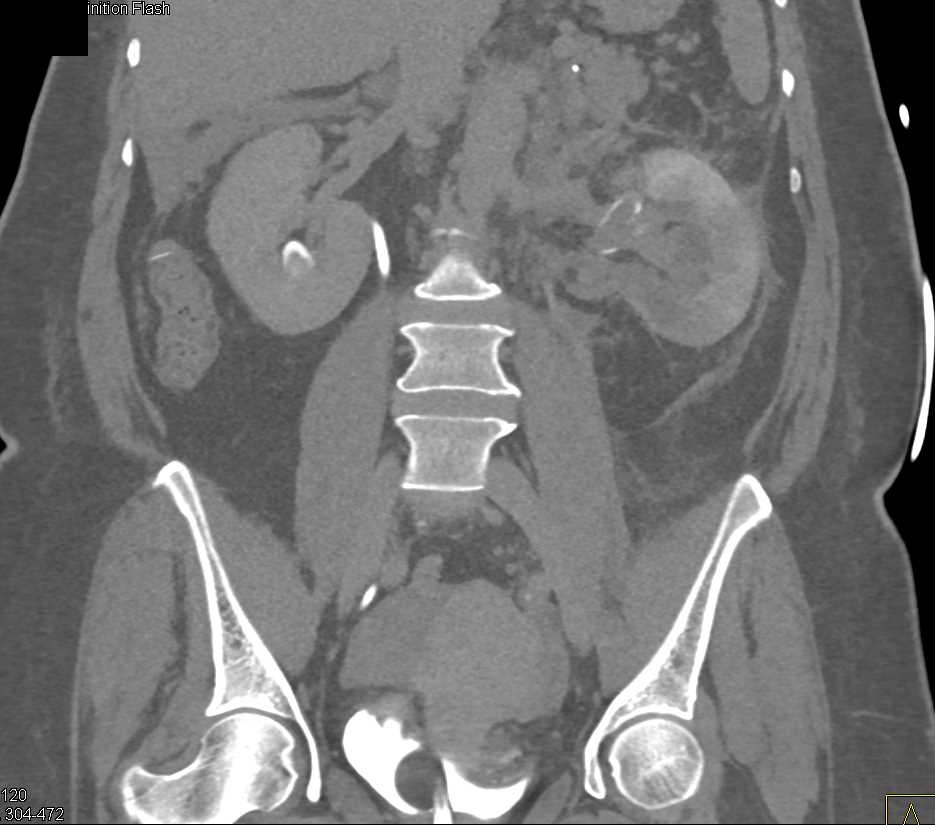

Acute Pyelonephritis Right Kidney